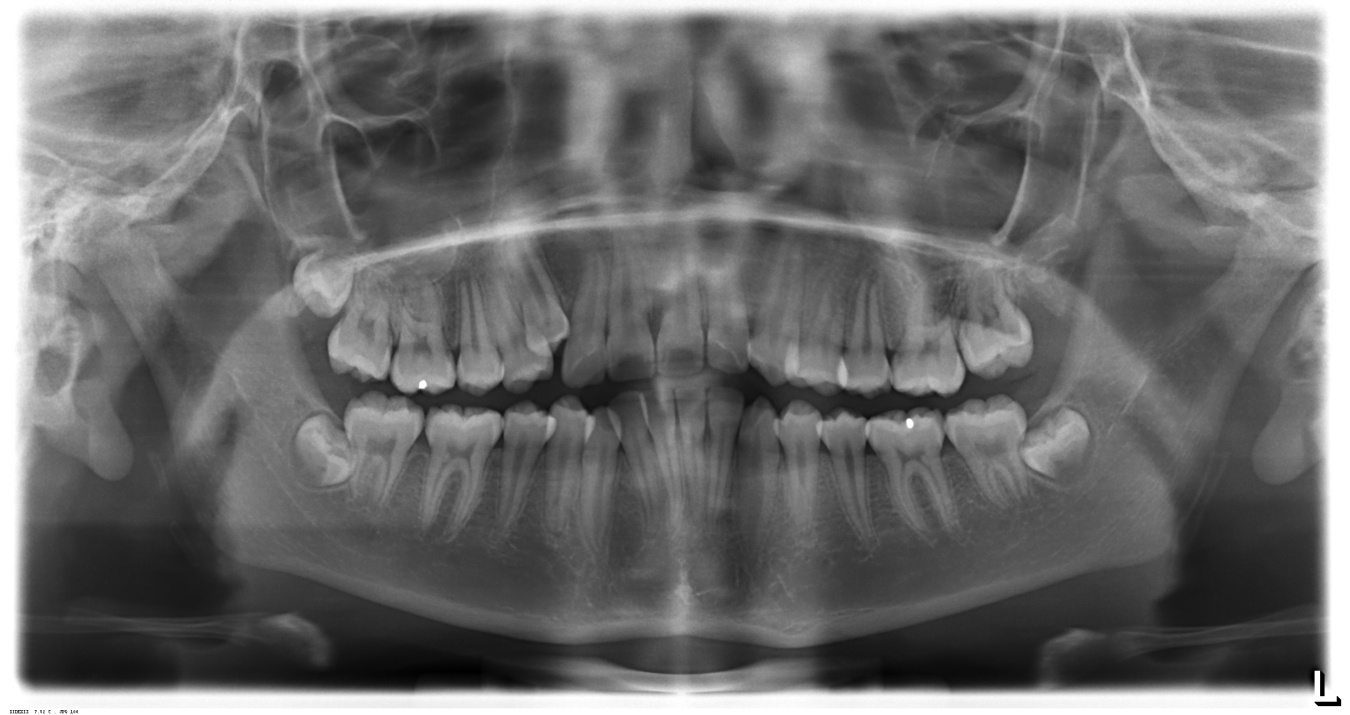

CASO 3. CALCULOS PULPARES

Dentro de la pulpa de los dientes se encuentran diversas formas de calcificaciones, con una frecuencia tal ,que se puede dudar acerca de si su presencia representa un estado patológico o solamente aspecto de las variaciones biológicas normales. Estas calcificaciones se pueden localizar en cualquier parte de la cámara pulpar y otras en el conducto radicular, inclusive en ambas localizaciones al mismo tiempo.

Los nódulos pulpares varían en su tamaño desde pequeñas partículas microscópicas hasta formaciones que ocupan casi toda la cámara pulpar.

Los nódulos pulpares son calcificaciones pulpares, sin causas conocidas y evolución impredecible, que consisten en concreciones de tejido muy calcificado y estructura laminada, las cuales se encuentran más frecuentemente en la cámara pulpar que en los conductos radiculares.

Las calcificaciones de la pulpa presentan un problema en el tratamiento endodontico y pueden tomar cada vez más difíciles estos procedimientos, en especial cuando son extensas o se adhieren a las paredes pulpares.